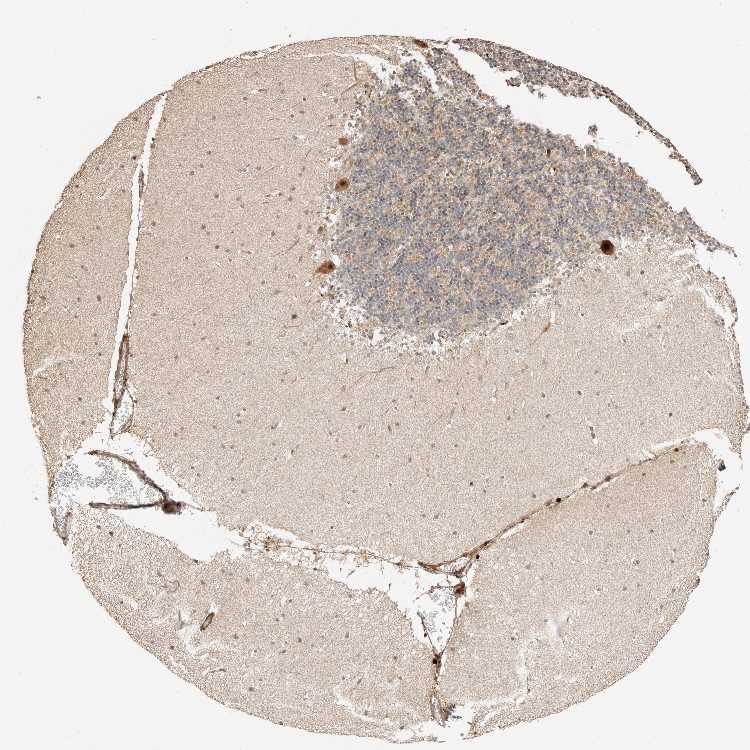

CEREBELLUM - Antibody stainingi

Antibody staining in the annotated cell types in the current human tissue is reported as not detected, low, medium, or high, based on conventional immunohistochemistry profiling in selected tissues. This score is based on the combination of the staining intensity and fraction of stained cells.

Each image is clickable and will lead to virtual microscopy that enables deeper exploration of all samples and also displays staining intensity scores, fraction scores and subcellular localization as well as patient and tissue information for each sample.

Antibody HPA024798

Purkinje cells High

Cells in granular layer Medium

Cells in molecular layer Medium